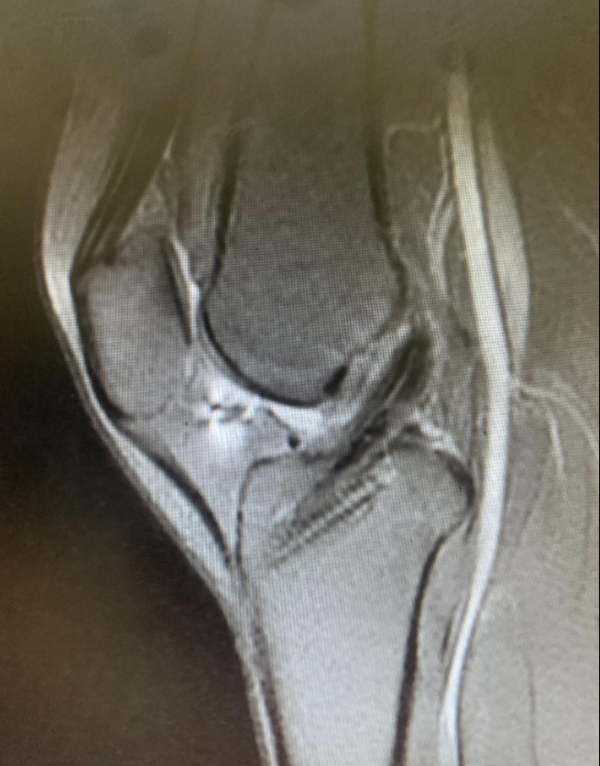

滑雪运动员术后重返训练场后复查MRI,重建韧带各项影像学指标都接近完美